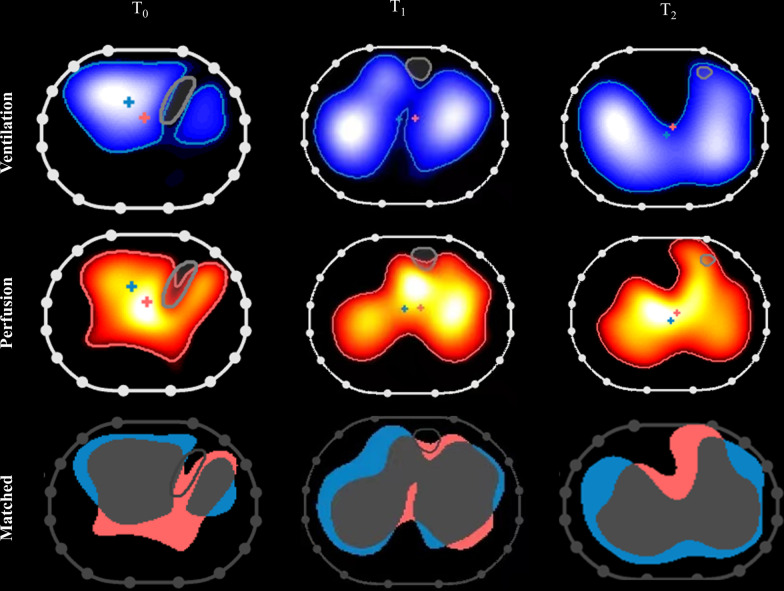

Measurements and main results: The regional distribution of ventilation and perfusion was analyzed based on EIT images and compared to the clinical variables regarding respiratory and hemodynamic status. Prolonged prone ventilation improved oxygenation in the ARDS patients. Based on EIT measurements, the distribution of ventilation was homogenized and dorsal lung ventilation was significantly improved by PP administration, while the effect of PP on lung perfusion was relatively mild, with increased dorsal lung perfusion observed. The ventilation-perfusion matched region was found to increase and correlate with the increased PaO2/FiO2 by PP, which was attributed mainly to reduced shunt in the lung.

Conclusions: Prolonged prone ventilation increased dorsal ventilation and perfusion, which resulted in improved ventilation-perfusion matching and oxygenation.